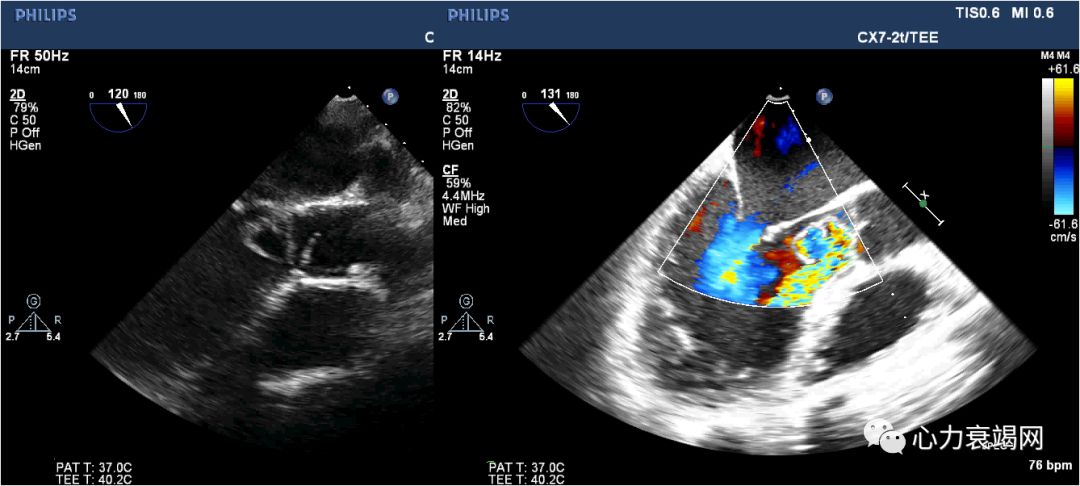

F/63

间断胸痛2月余,憋气伴双下肢水肿1月

血常规:

WBC11.81*10^9/L,EOS 4.14*109/L,EOS%35%,便寄生虫(-)*3

T-IgE 569.0KU/L↑

CTnI 1.12 → 2.67ng/ml;BNP378ng/L

支气管哮喘十余年。对花粉等多种物质过敏。

胸片:左肺中野团絮状高密度影,边界不清,双侧胸腔积液;

冠脉造影:右冠轻度动脉硬化,前降支、回旋支大致正常

➤ 典型的CSS分病程初始常为哮喘、过敏性鼻炎,此后出现心内膜心肌的嗜酸性粒细胞浸润。

引起类似Loftier心内膜炎的心脏病变。

心室心尖闭塞及限制性心肌病,心腔内血栓形成,心内膜和心肌间质纤维化。

➤ 部分患者并不出现典型的Loftier心内膜炎的改变,而主要表现为坏死性心肌血管炎导致的心脏扩大、心力衰竭或心律失常。

➤ 心包炎、心肌梗死